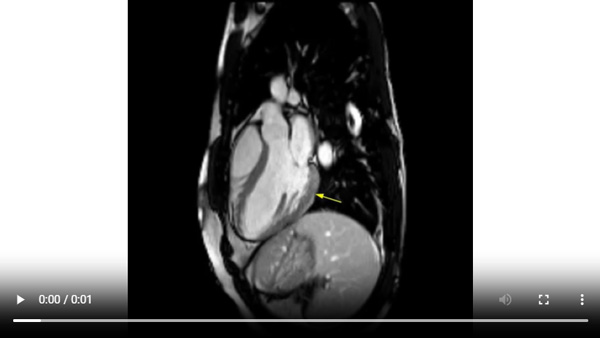

Figure 4A : Séquence de rehaussement tardif - Coupes petit-axe

Figure 4B : Séquence de rehaussement tardif - Coupes long-axes

Présence d’une zone de rehaussement tardif sous-épicardique aux niveaux inféro-latéro-basal et inféro-basal (zones blanches, flèches jaunes) comparée au reste du myocarde (noir).

Retenez le dogme selon lequel le muscle cardiaque sain apparaît toujours « noir » sur les séquences de rehaussement tardif.

Visualisation d’un rehaussement myocardique systolique à prédominance sous-épicardique sur les cinés long-axe (2 cavités et 3 cavités) acquises après injection de gadolinium. C’est un signe assez évocateur d’œdème myocardique, qui est souvent retrouvé en cas de myocardite aiguë.